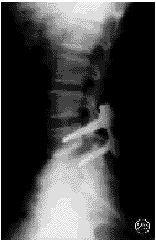

图1 患者男,50岁。术前X线片示L4,5Ⅰ度滑脱移位

1a 术前X线正位片 1b 术前X线侧位片